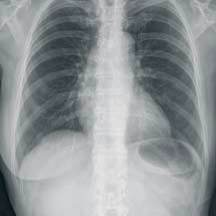

High image quality and throughput without compromise

The CR 30-X uses Agfa’s long-term experience in CR and

intelligent image processing to provide image quality

without compromise.

It scans at a spatial resolution of 10 pixel/mm before processing

the image using MUSICA, Agfa’s patented, market-leading

intelligent image processing software. By scanning the phosphor

plate at the full width of 43 cm, the CR 30-X combines high

quality with high throughput.

image quality